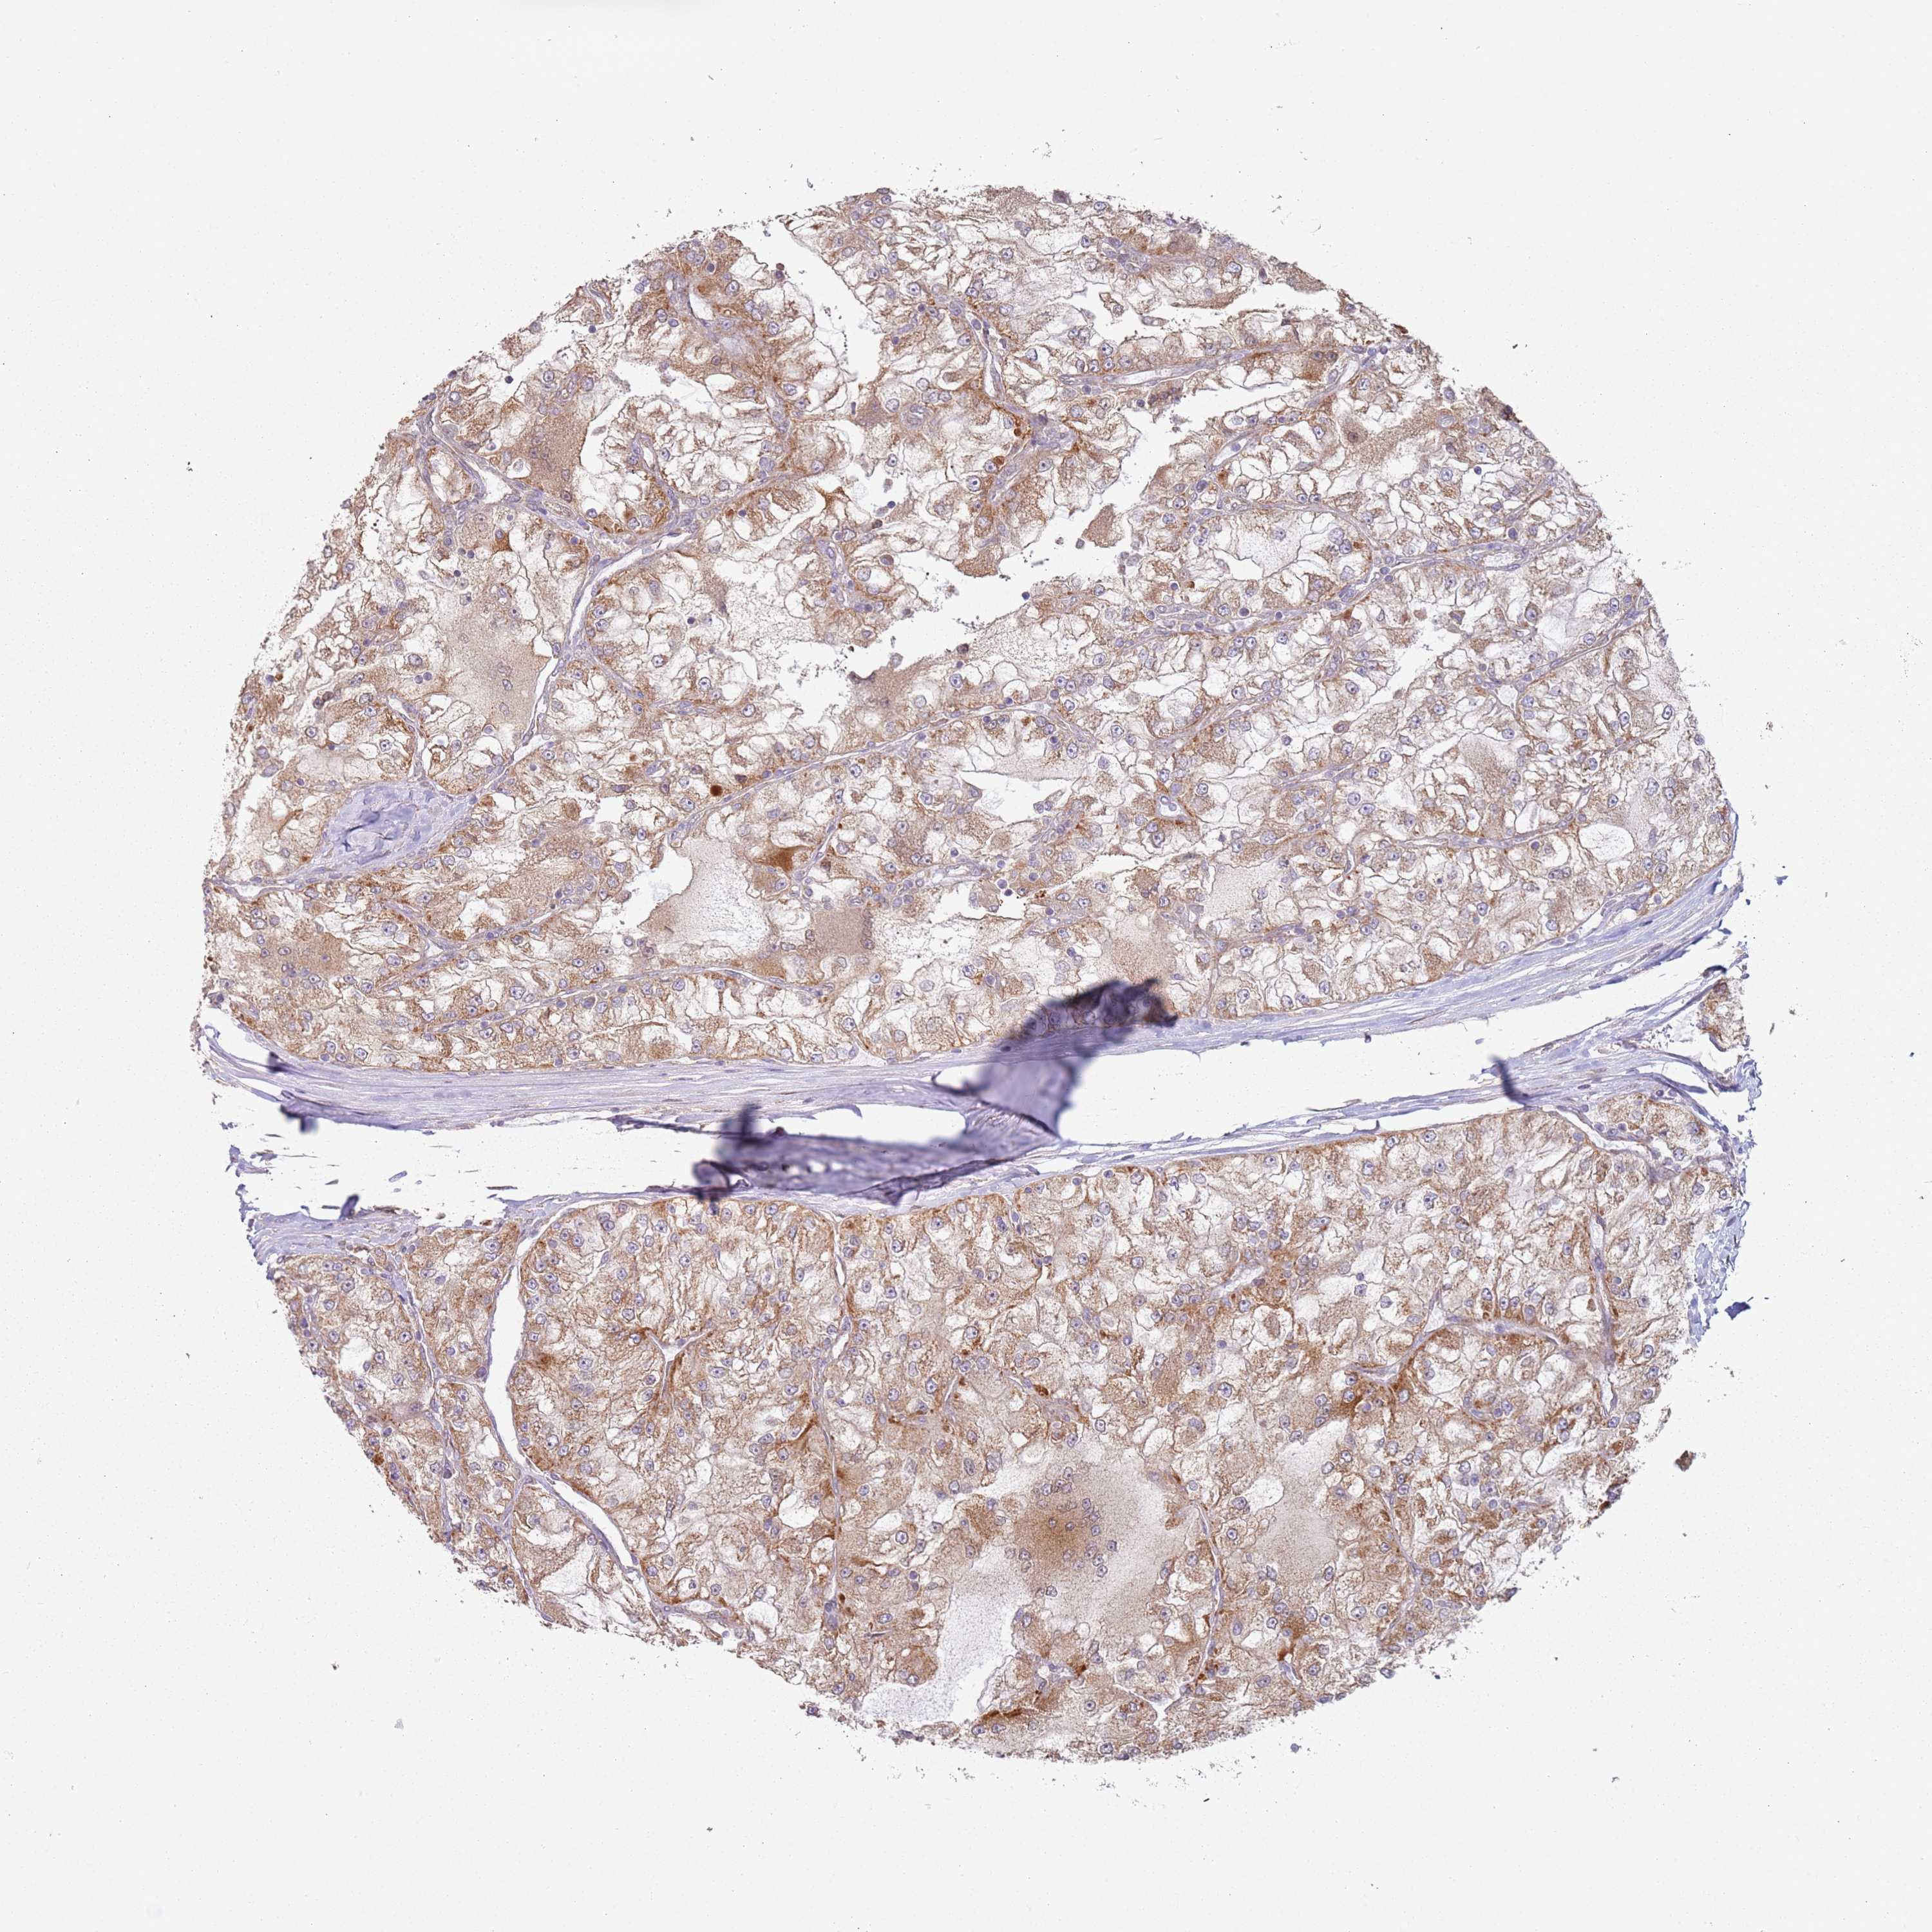

KIDNEY RENAL CLEAR CELL CARCINOMA (VALIDATION) - Interactive survival scatter ploti

The Survival Scatter plot shows the clinical status (i.e. dead or alive) for all individuals in the patient cohort, based on the same data that underlies the corresponding Kaplan-Meier plots. Patients that are alive at last time for follow-up are shown in blue and patients who have died during the study are shown in red.

The x-axis shows the expression levels (FPKM) of the investigated gene in the tumor tissue at the time of diagnosis. The y-axis shows the follow-up time after diagnosis (years). Both axes are complimented with kernel density curves demonstrating the data density over the axes. The top density plot shows the expression levels (FPKM) distribution among dead (red) and alive patients (blue). The right density plot shows the data density of the survived years of dead patients with high and low expression levels respectively, stratified using the cutoff indicated by the vertical dashed line through the Survival Scatter plot. This cutoff is automatically defined based on the FPKM cutoff that minimizes the p-score. The cutoff can be changed by dragging the vertical line or by entering a cutoff value in the square labeled "Current cut-off".

Under the Survival Scatter plot the p-score landscape (black curve; left axis) is shown together with dead median separation (red curve; right axis). Dead median separation is the difference in median mRNA expression between patients who have died with high and low expression, respectively. It is calculated as follows: median FPKM expression of dead patients with high expression - median FPKM expression of dead patients with low expression. This is intended to aid the user in visually exploring custom cutoffs and the associated p-scores and dead median separation.

Individual patient data is displayed and can be filtered by clicking on one or more of the category buttons on the top of the page. Categories describing expression level and patient information include: high, low, alive, dead, female, male and tumor stages. The scale of the x-axis can be toggled between linear and log-scale by clicking on the "x log" button. Mouse-over function shows TCGA ID, patient information and mRNA expression (FPKM) for each patient.

& Survival analysisi

Kaplan-Meier plots summarize results from analysis of correlation between mRNA expression level and patient survival. Patients were divided based on level of expression into one of the two groups "low" (under cut off) or "high" (over cut off). X-axis shows time for survival (years) and y-axis shows the probability of survival, where 1.0 corresponds to 100 percent.

HNRNPLL is not prognostic in Kidney Renal Clear Cell Carcinoma (validation)

Best expression cut offi

Based on the FPKM value of each gene, patients were classified into two groups and association between prognosis (survival) and gene expression (FPKM) was examined. The best expression cut-off refers the FPKM value that yields maximal difference with regard to survival between the two groups at the lowest log-rank P-value. Best expression cut-off was selected based on survival analysis .

When clicking on this number, the vertical dashed line indicating cut-off, the interactive survival plot, and the Kaplan-Meier curve will be adjusted to show results based on the best expression cut-off.

: 24.95

P scorei

Log-rank P value for Kaplan-Meier plot showing results from analysis of correlation between mRNA expression level and patient survival.

N/A

5-year survival highi

5-year survival for patients with higher expression than the expression cutoff.

For melanoma and glioma, 3-year survival is shown.

5-year survival lowi

5-year survival for patients with lower expression than the expression cutoff.

TCGA RNA samplesi

RNA-seq data is reported as average FPKM (number Fragments Per Kilobase of exon per Million reads), generated by the The Cancer Genome Atlas (TCGA) .

Normal distribution across the dataset is visualized with box plots, shown as median and 25th and 75th percentiles. Points are displayed as outliers if they are above or below 1.5 times the interquartile range. FPKM values of the individual samples are presented next to the box plot.

Average pTPM 23.1

Number of samples 100